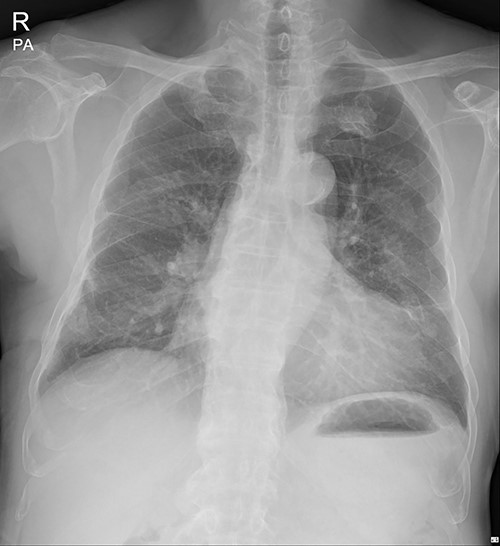

Immediate postoperative chest X-ray after plates removal (24 February 2022).

The patient visited the outpatient clinic on 07 March 2022, for stitches removal, complaining of mild discomfort on the operation site (Fig. 3.). Chest X-ray showed a large, localized submuscular emphysema between the rib cage and the SAM. The surgical wound was clear. Stitches were removed as planned, and the patient was asked to revisit the outpatient clinic 3 days later.